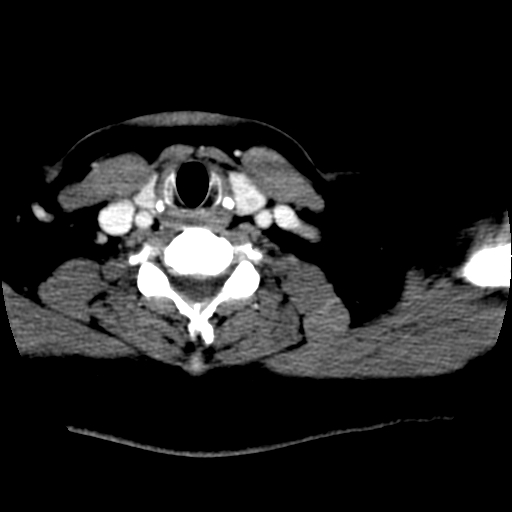

左右叶都有,峡部也受累,有钙化,考虑结甲可能性大。

甲状腺东西特异性不强,结节很小有很多是恶性,有的很怕人却是良性。